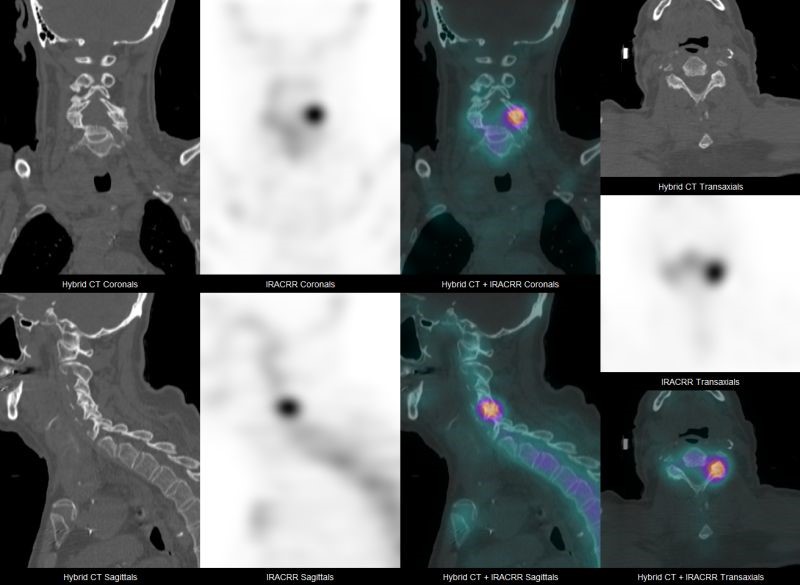

At SRNM, we offer Medicare-funded FDG PET scans (Items 61612 & 61614) for the staging, treatment response, and recurrence of rare and uncommon cancers.